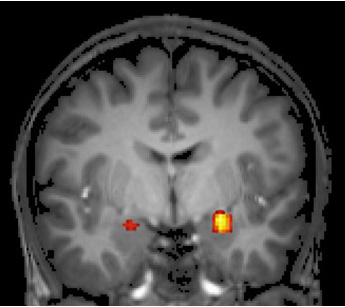

Evidence suggests that the behavioral manipulation may work through the same molecular mechanisms in the brain’s fear hub, the amygdala (yellow/red), as experimental medications under study for quelling traumatic emotional memories. Functional magnetic resonance imaging scan showing activation of the amygdala.